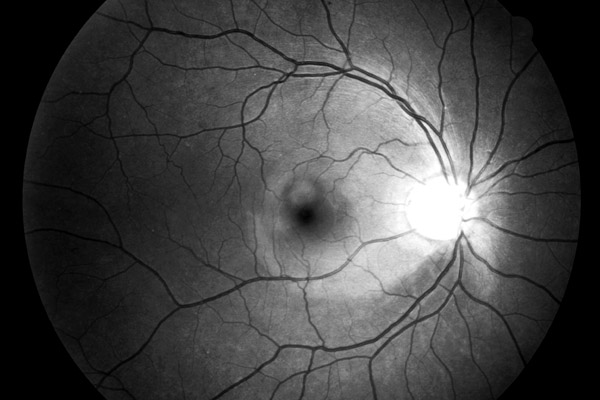

Vrstva nervových vláken

Oftalmo-neurologická diagnostika 1956, Michelem popsaný obraz si můžeme kdykoliv vyvolat, vyšetřujeme-li oční pozadí podle Vogtova návrhu bezčerveným světlem.

The temporal raphe of the human retina Amer.J.ophthal. 62:926/1966, popsal předěl ve vrstvě nervových vláken temporálně od makuly mezi horní a dolní polovinou sítnice.